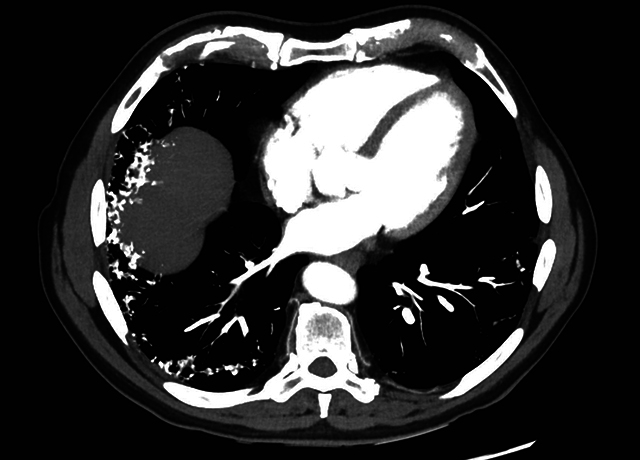

Teaching point: Dendriform pulmonary ossifications (DPO) are a rare form of diffuse pulmonary ossifications, in which these ossifications are organised in dendrite-like lines in the periphery of the bases of the lung, most commonly attributed to underlying interstitial lung disease (ILD), but can also be found in patients with chronic aspiration if no other CT findings of ILD are present.

教学要点树枝状肺骨化(DPO)是一种罕见的弥漫性肺骨化,这些骨化呈树枝状排列在肺底部外围,最常见的原因是潜在的间质性肺病(ILD),但如果 CT 没有发现其他 ILD 病变,也可在慢性吸入性肺病患者中发现。